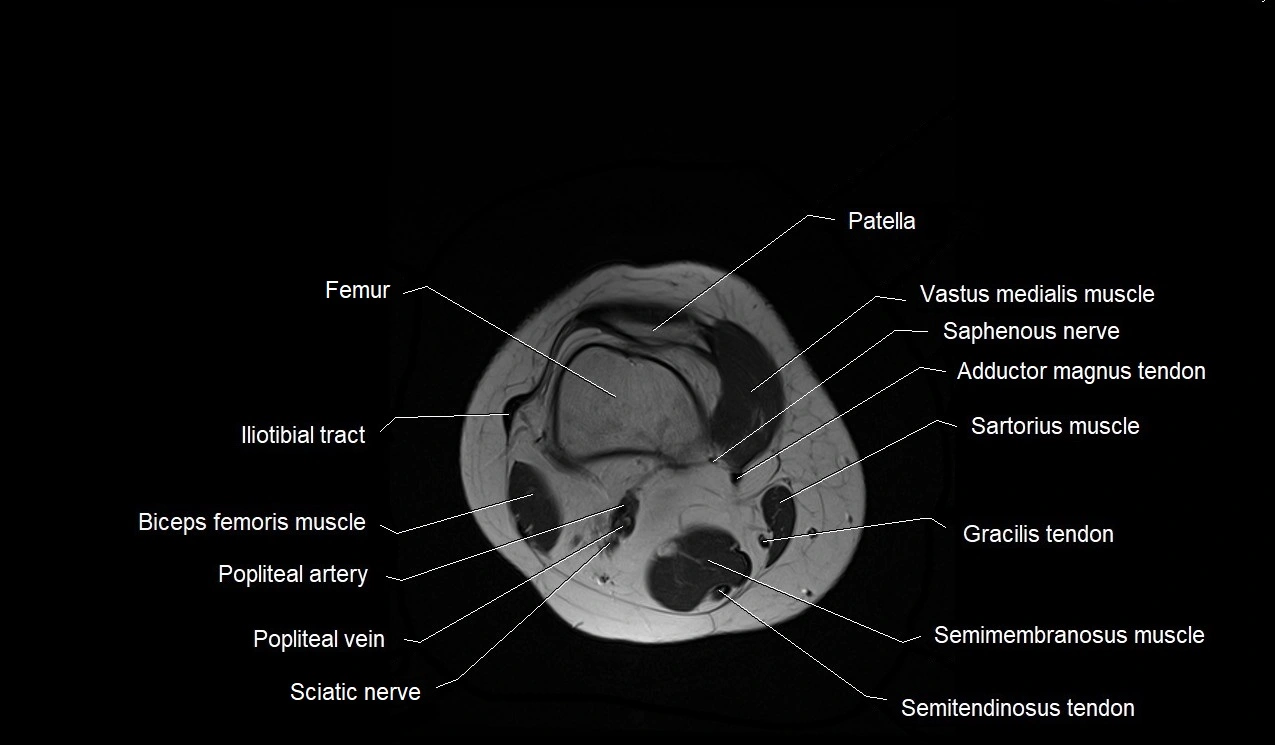

- Patella

- Femur

- Iliotibial tract

- Popliteal artery

- Popliteal vein

- Saphenous nerve

- Sartorius muscle

- Semimembranosus muscle

- Semitendinosus muscle

- Gracilis muscle

- Gracilis tendon (Distal)

- Biceps femoris muscle (Long head)